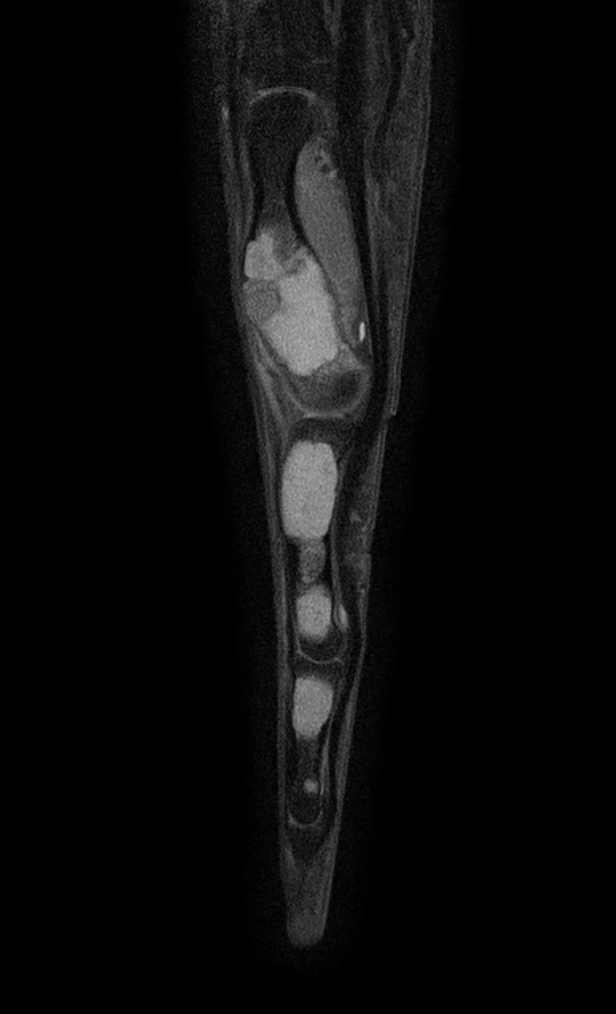

Sagittal T1w mDIXON XD TSE (Water only)

Sagittal T1w mDIXON XD TSE (In Phase)

Sagittal T1w mDIXON XD TSE (Partial FatSat)